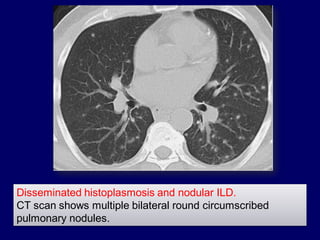

Disseminated histoplasmosis and nodular ILD.

CT scan shows multiple bilateral round circumscribed

pulmonary nodules.

Disseminated histoplasmosis andnodular ILD. CT scan shows multiple bilateral round circumscribed pulmonary nodules.